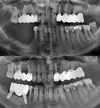

Implant tedavisi